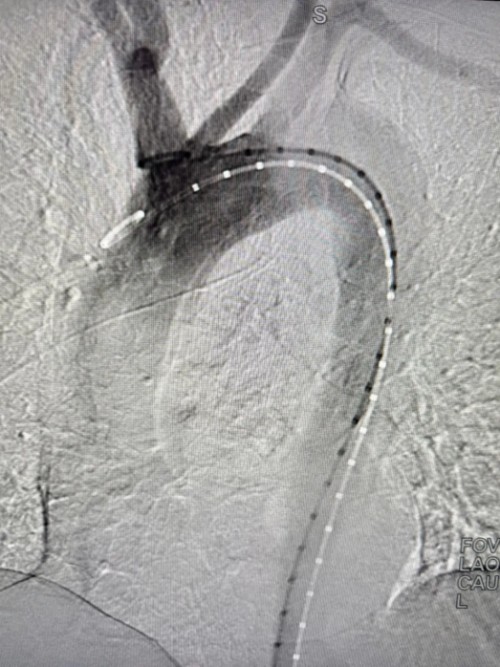

病情危急,刻不容缓。血管外科主任汪岩立即组织团队紧急研判,结合患者病情与影像学资料,果断决定即刻实施主动脉腔内隔绝术,该微创术式具有创伤小、恢复快、效果确切等优点,是救治主动脉夹层的优选方案。

手术室内,汪岩主任团队精准操作、默契配合,顺利完成支架置入以隔绝动脉破口。术后患者背部剧痛即刻缓解,生命体征迅速稳定,手术圆满成功。从急诊接诊、多学科会诊、影像确诊到急诊手术完成,全院各科室环环相扣、无缝衔接、全力抢救,以专业与速度筑牢了生命防线。